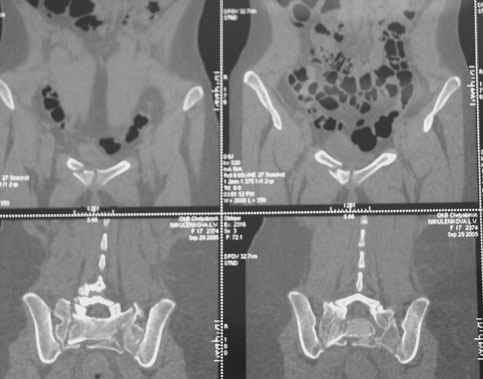

Травма 21.августа 2005г. На девочку в лесу упала береза. Доставлена в ближайшую ЦРБ. При поступлении установлен диагноз: Травматический шок 2-3 ст. Тупая травма живота. Забрюшинная гематома. Перелом костей таза с нарушением целостности тазового кольца. Перелом лонной и седалищной костей справа. Перелом поперечных отростков L3 - L5. Разрыв КПС справа. При поступлении выполнена диагностическая лапароскопия — выявлена обширная забрюшинная гематома. Было наложено скелетное вытяжение за бугристости обеих б/берцовых костей, больная уложена в гамак. Через неделю скелетное вытяжение демонтировано, гамак снят. Девочка уложена в положение «лягушки». Контрольные рентгенограммы через 4 недели после травмы. Заподозрен перелом дужки L5. Больная 26 сентября 2005 г. переведена в областную больницу в отделение детской ортопедии. При поступлении в локальном статусе: пальпация и перкуссия остистых и поперечных отростков L4-5 болезненная. Пальпация костей таза б/болезненная. С-м натяжения слабо положителен. Осевая нагрузка положительная. Движения в т/б суставах ограничены, болезненны. C-м прилипшей пятки отрицательный. C-м Ларрея и Варнейля отрицательный. Периферическая гемодинамика не нарушена.Неврологический статус: вторичная двусторонняя радикулопатия L5-S1. 29 сентября произведена компьютерная томография позвоночника и таза.

Судя по томограммам, радикулопатия может быть из-за компресии "конского хвоста" смещенным крестцовым позвонком, это хорошо видно на втором слева снимке. Если этот сегмент будет нестабилен и будет сохраняться неврологическая симптоматика, придется оперировать. Если неврологическая симптоматика уйдет и перелом стабилизируется, то можно обойтись без операции.